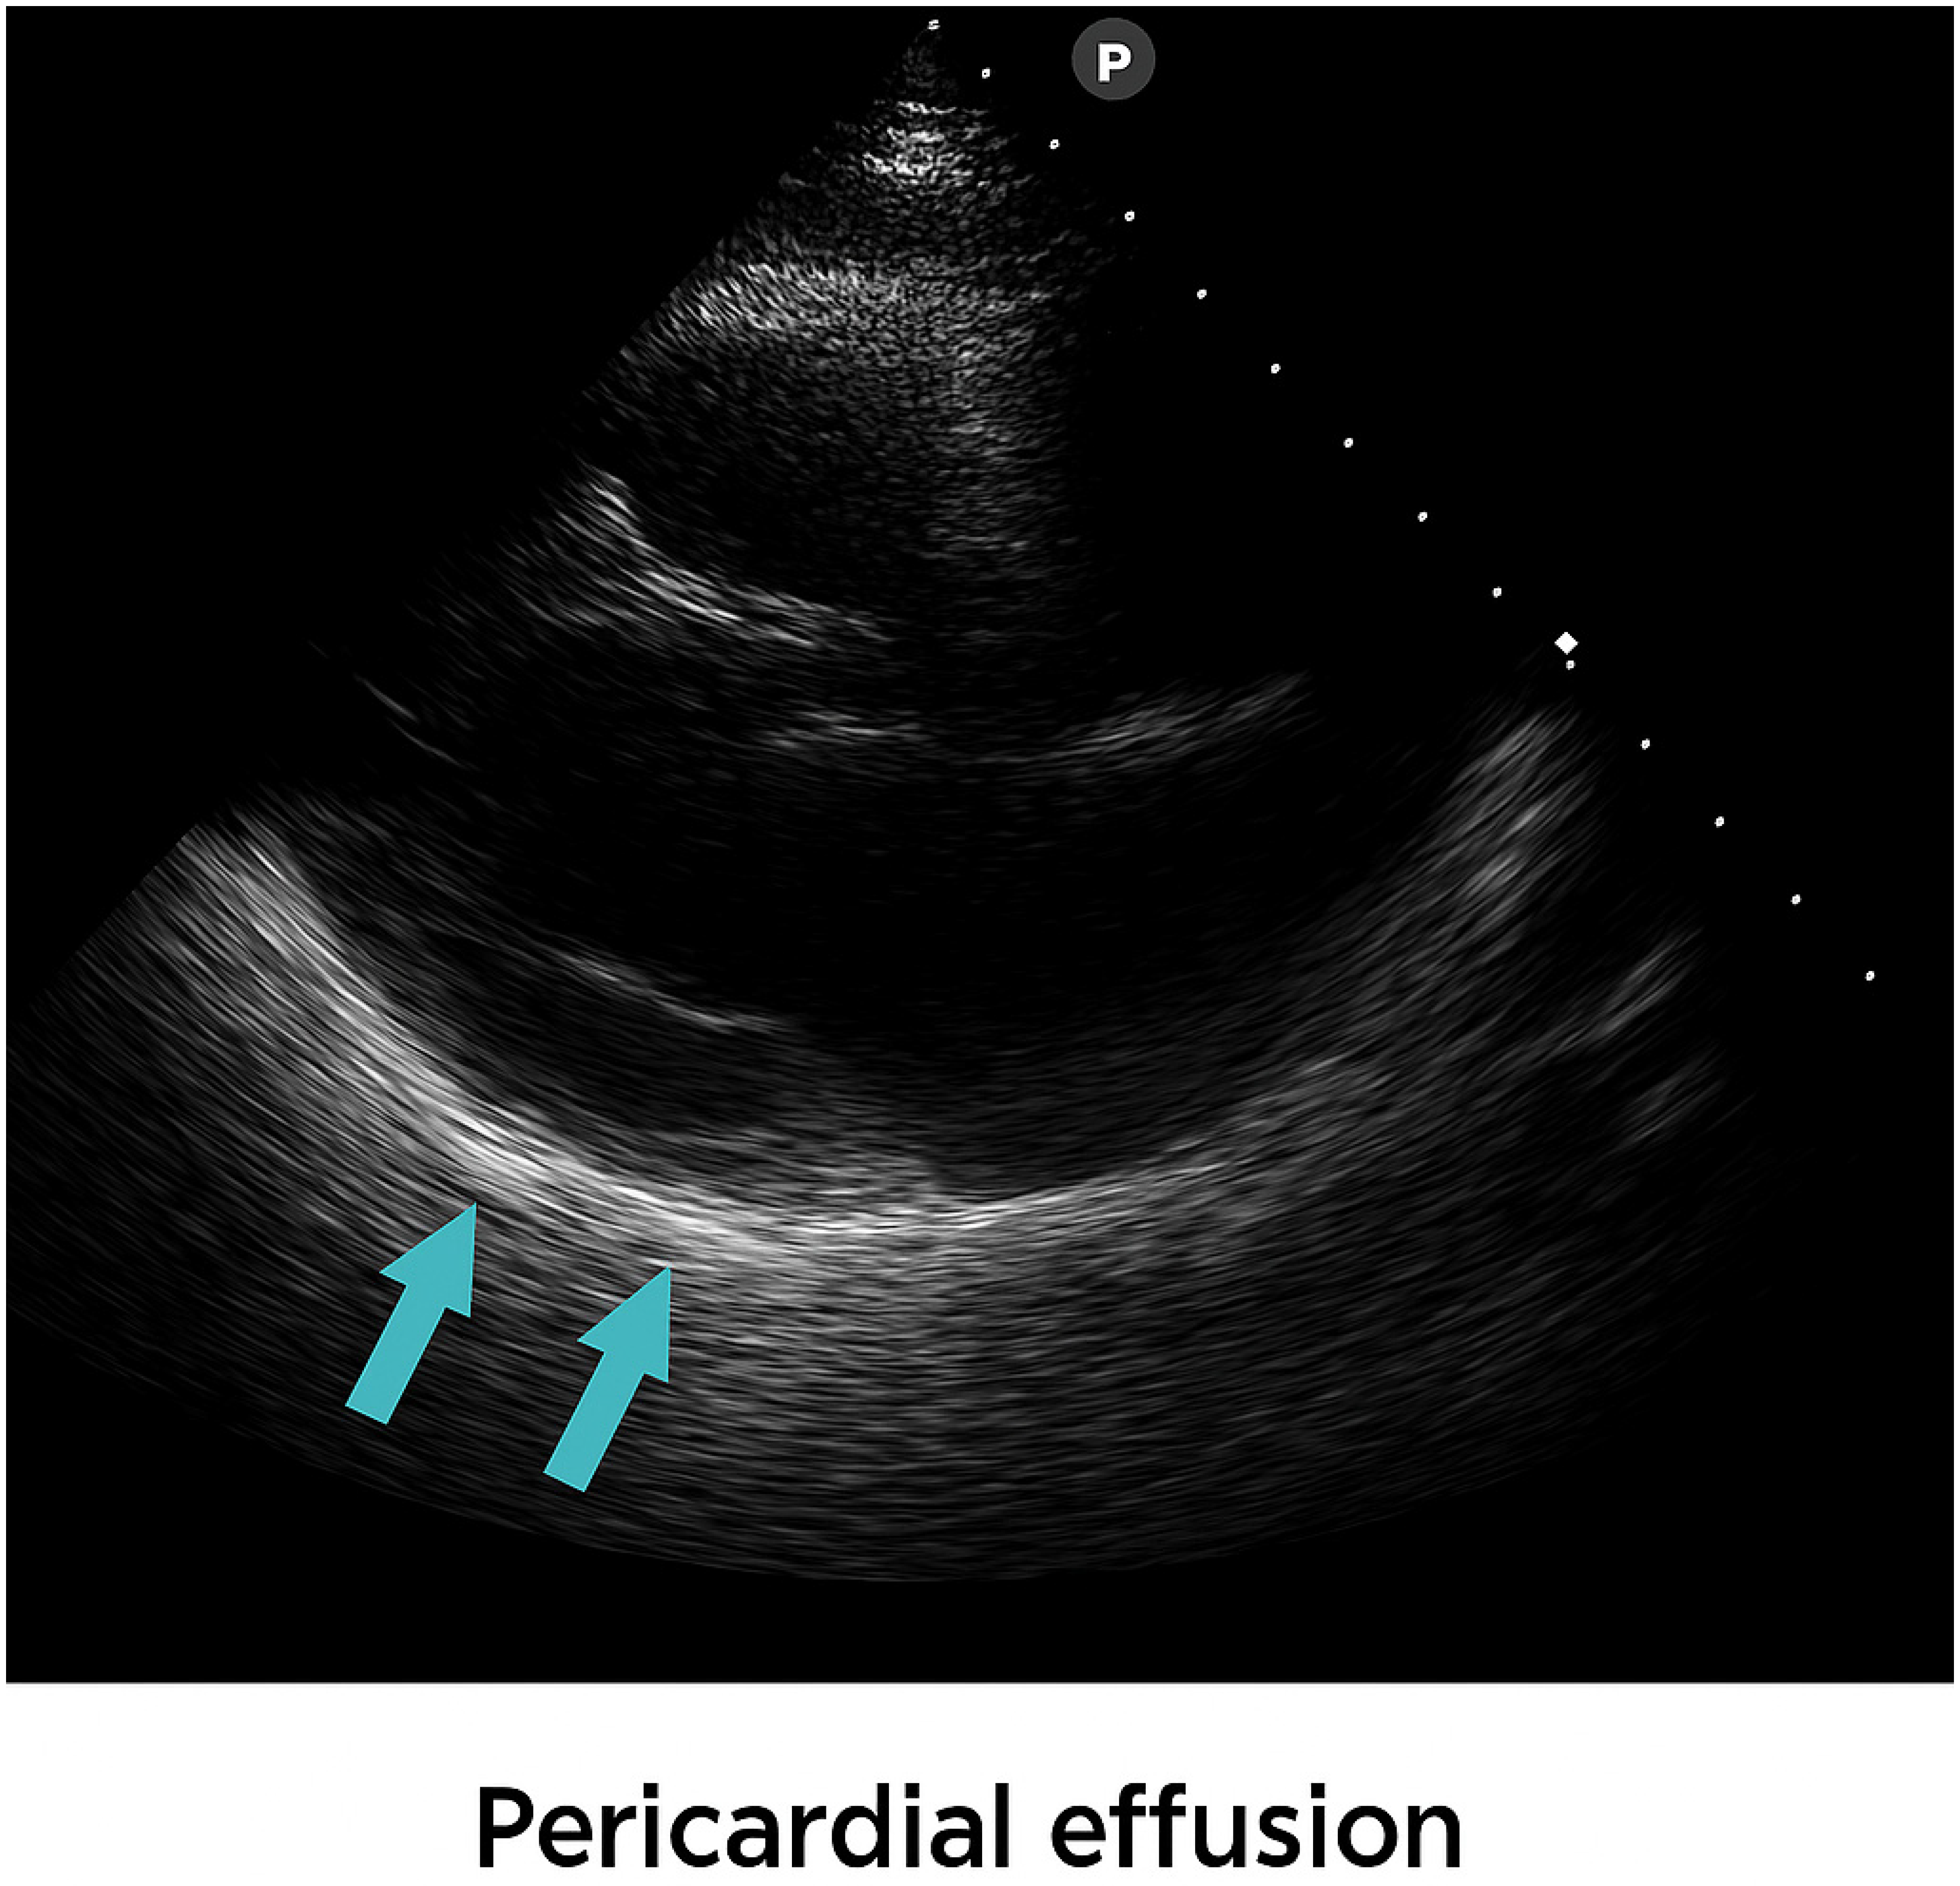

| Pericardial fluid | 0.5 cm | 0.3 cm | ||||||||